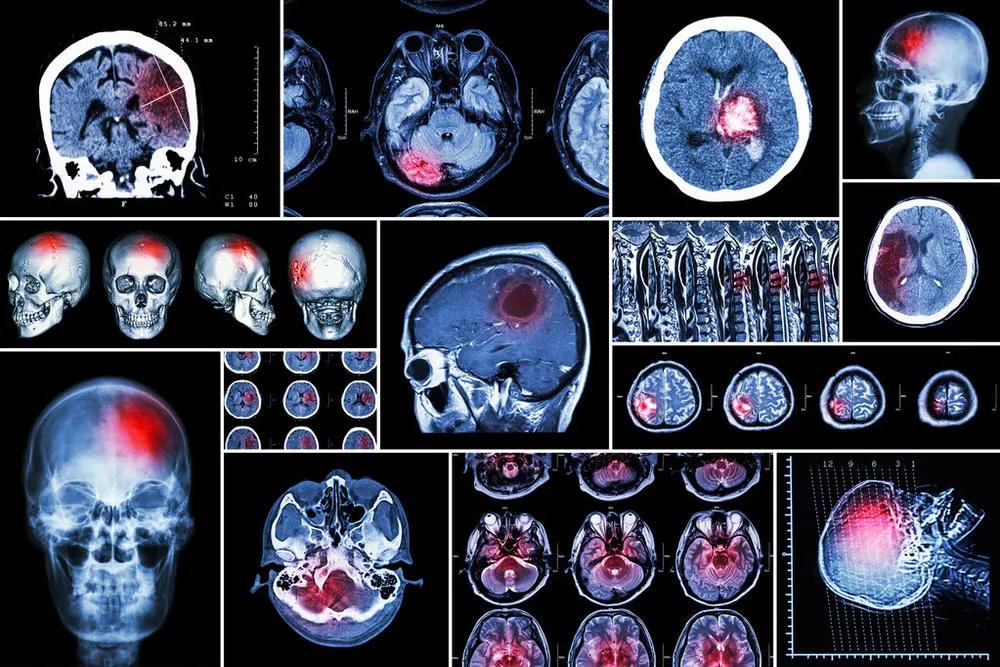

复旦大学附属中山医院骨科主任董健教授说:“尽管我们人体有很多器官,如前列腺、肾脏等,但肿瘤细胞有自己偏好的‘殖民地’—— 脑、肝和骨是人体三大肿瘤转移高发部位 ,转移性肿瘤排在

- 第一的是 脑转移 ,

- 第二是 肝脏转移 ,

- 第三便是 骨转移 ,而骨转移中涉及最多的部位就是 脊柱 。”

脊柱是血供器官,血管丰富,肿瘤细胞能随流经的血液定植在椎体,30%~70%的恶性肿瘤会出现脊柱转移,占据脊柱椎体、破坏脊柱的生物力学稳定性、压迫神经脊髓,从而带来剧烈疼痛甚至导致瘫痪,严重影响患者的生存质量。